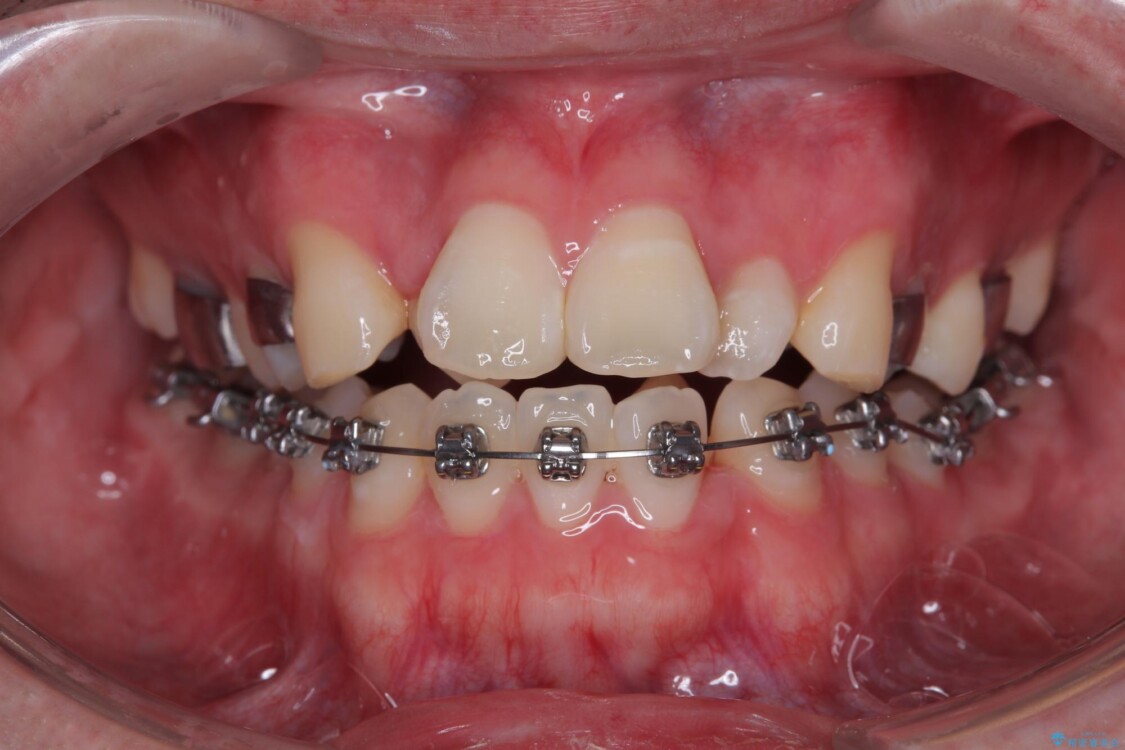

治療方針

このような歯列の狭さに起因するデコボコを改善するために、**MARPE(骨に固定する上顎急速拡大装置)**を使用して、上顎の横幅を拡大し、これにより歯が並ぶためのスペースを確保し、メタルブラケットを用いて歯列を整えていく計画としました。

費用面を考慮し、装置はコストパフォーマンスに優れたメタルブラケットを選択。見た目よりも機能と効果を重視したい方には特におすすめの選択肢です。

治療途中

• 1年でここまで変わる!歯列のがたつきと正中のズレを改善した矯正治療(メタルブラケット×MARPE) 治療途中画像